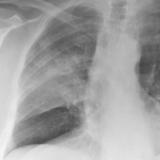

Pancoast

Album: Pancoast

Date: 03/03/2004

Size: 19 items

Views: 39221